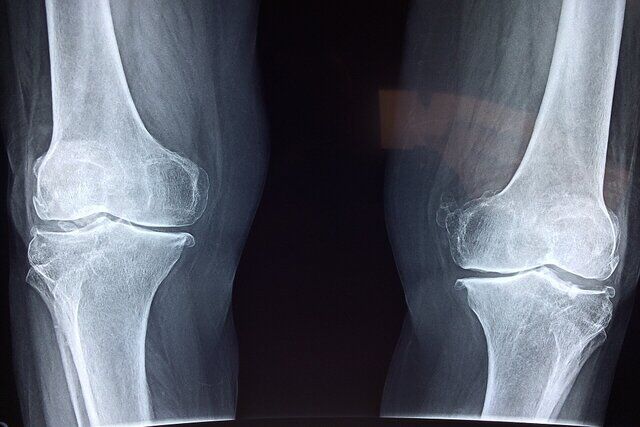

سید مهدی میرغضنفری، معاون تعالی دفتر طب ایرانی و مکمل وزارت بهداشت با اشاره به شیوع پوکی استخوان خصوصا در سنین بالا، نگاه طب ایرانی به این بیماری را تشریح کرد و گفت: از دیدگاه مشترک طب ایرانی و فیزیولوژی مدرن، استخوان یک بافت زنده و پویا است که همواره در حال تخریب و بازسازی است و برای حفظ سلامت آن، ضروری است که از طریق جریان خون، غذای باکیفیت و مناسبی دریافت کند.

وی تاکید کرد: اگر خون کیفیت لازم را نداشته باشد، تغذیه مناسبی برای استخوان صورت نمیگیرد و مواد ضروری برای رشد و بازسازی به آن نمیرسد. در نتیجه استخوان بهتدریج ضعیفتر میشود که به این حالت اصطلاحاً پوکی استخوان گفته میشود.